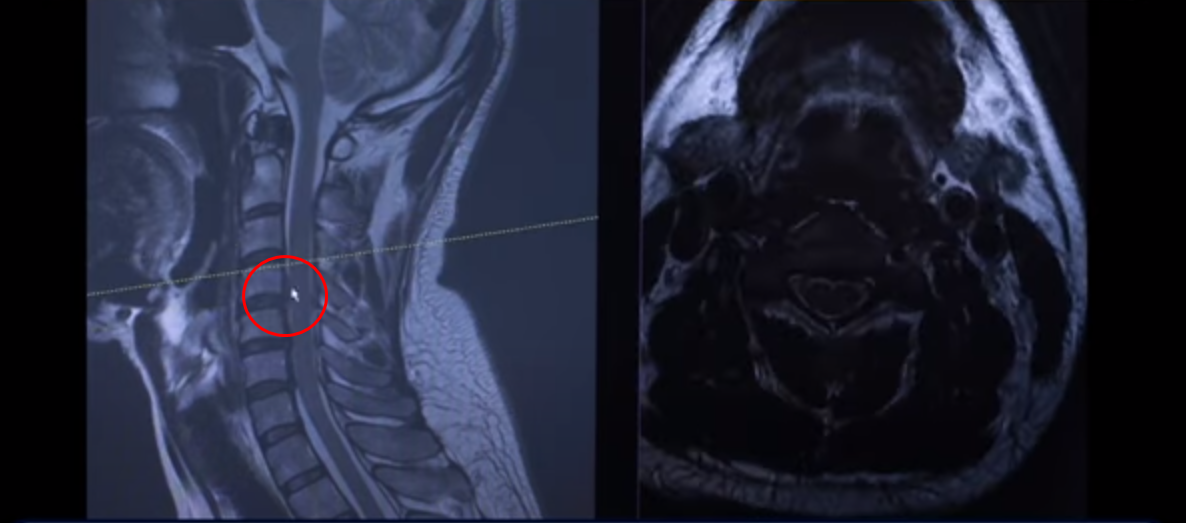

41세 목디스크 환자분 MRI 보도록 하겠습니다. 이분은 한 5년 동안 계속 목에 담결림 증상을 호소하시던 분입니다.

여기 MRI를 보시면 이렇게 세 마디에 퇴행성 목디스크가 있습니다. 보시다시피 희미하게 밀려서 올라간 게 보이실 겁니다. 디스크가 밀려서 올라간 겁니다.

그 다음 마디를 보시면 여기도 이렇게 좀 튀어나와 있습니다.

이 환자분 증상이 목에 담결림 증상 외에도 왼쪽 어깨 쪽 증상과 왼쪽 손의 저림 증상입니다. 그래서 이것 때문에 왼쪽에 증상이 있다 이렇게 보시면 됩니다.